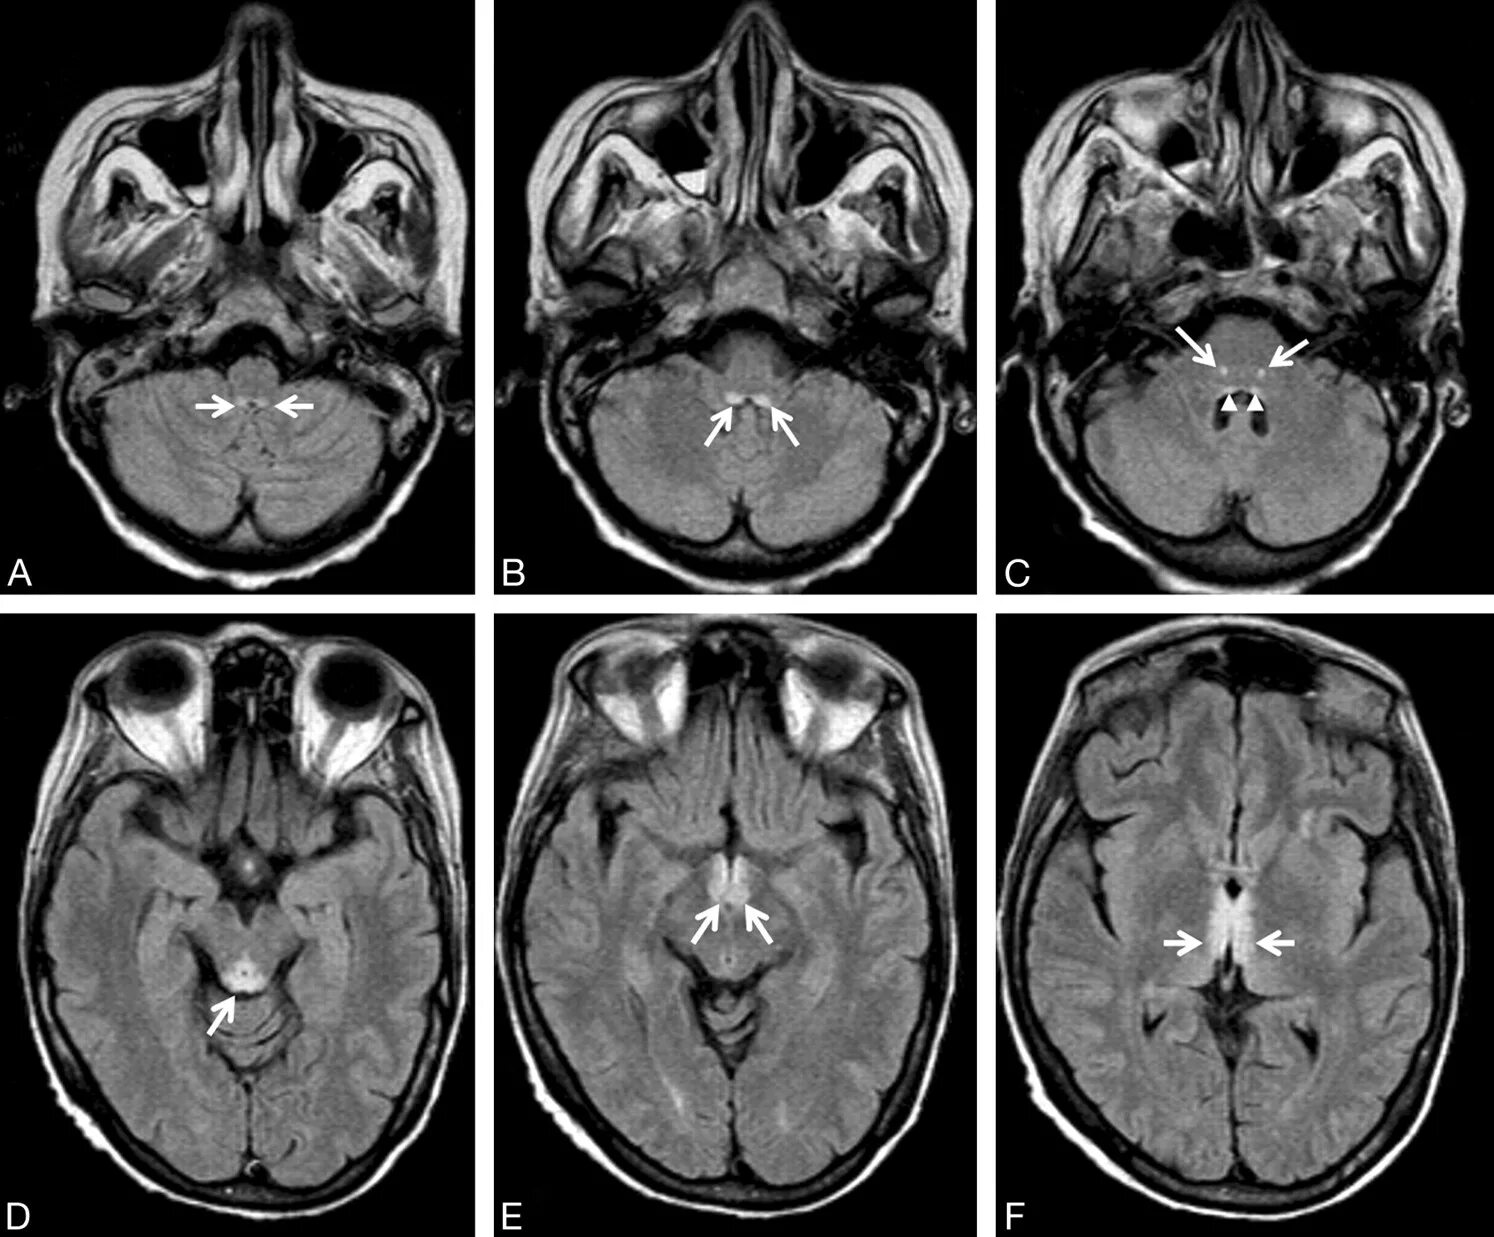

Гая вернике